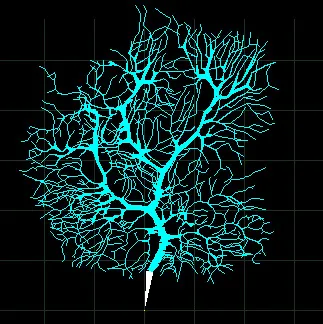

Section titled “Deeper into the Brain”In medical school, after dissection, we moved on to microscopic study of the body. On a microscopic level, we could see how complex and delicate the brain cells are. In the image below, you can see two nerve cells (also called neurons), with connections that become very fine, almost like steel wool, in the left of the image. Brain cells have a compact cell body, sometimes called the soma.

From the soma, many tiny extensions reach out and connect with other nerve cells. These very thin cell fibers are more susceptible to damage than cells with other shapes. A nerve cell's bristly shape is distinctly different from the round shape of a skin cells or the rod shape of a muscle cell. For comparison, click here to see images of skin and muscle cells. In next month's newsletter, we'll talk more about the vulnerability of nerve cells and how we can protect them, but first, let's see how nerve cells operate.

Nerve fibers are specialized to bring in or send out signals. The "input" end of the neuron has many "dendrites" (from the Latin word "tree") that bring signals in to the main cell body (soma). The "output", called the axon, may be quite long (if it has to reach all the way to the foot, for example). The axon separates into many terminals, which stimulate other cells. Each neuron might have several thousand input dendrites and a similar number of terminal outputs.

The image below will give you a better idea of the complexity of just the input end of a nerve cell. This image shows the input end of a cell that helps control of our muscular system. The main cell body is below the picture, connecting to the white stump at the bottom of the image.